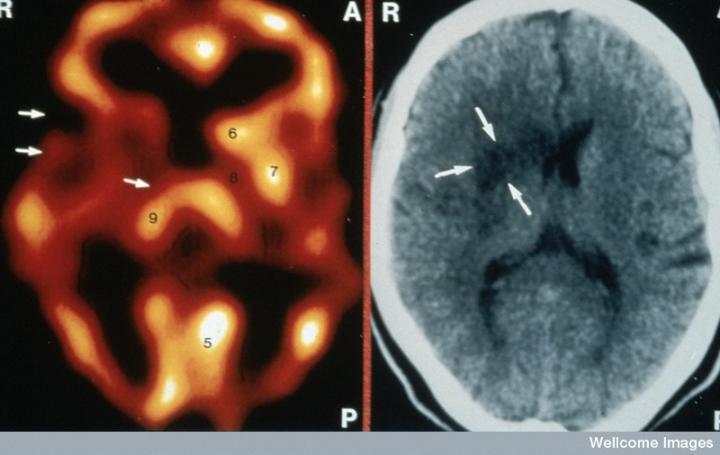

左側(cè)的血流圖比右側(cè)的X射線CT掃描顯示出更多的中風(fēng)損傷

慢性中風(fēng)患者的腦成像

CT掃描的主圖顯示左側(cè)有一些中風(fēng)損傷,由 Wellcome Images提供。Wellcome Photo Library提供的慢性中風(fēng)的附加圖像 ,Wellcome Images,QL 從胚胎干細(xì)胞培養(yǎng)的神經(jīng)元。Ying & A. Smith, Wellcome Images 和 Yirui Sun, Wellcome Images 移植的小鼠神經(jīng)干細(xì)胞。